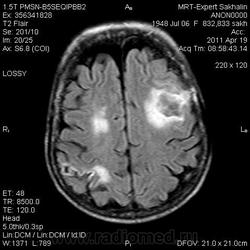

склоняюсь к кровизлиянию в левой теменной долей, начало перехода острой стадии в раннюю подострую( по периферии определяется повышение МРС по Т1 ВИ -метгемоглобин). Справа -старые кортикальные постишемческие глиозно-атрофические изменения. Контрастируется , вероятно за счет формирования участков ангионеогенза.

Это демиелинизирующий процесс, острая стадия, причем с геморрагическим пропитыванием в центре пораженных участков. В принципе, соответствует тяжелому рассеяному склерозу, хотя может быть и геморрагическая форма ОДЭМ. Также могут быть мозговые проявления системного васкулита: надо знать анамнез.

На фоне ДЭП изменений МР-картина ОНМК по ишемическому типу в бассейне ЛСМА с участками геморрагического пропитывания. Аналогичный участок но в более поздней фазе в задних конвнкситальных отделах правой теменной доли.

А мне постконтрастные не нравятся - ну не укладываются они в ОДЭМ и в ОНМК.

О.С., я согласен, что контрастирование нехарактерно для ОНМК, ведь в подострую стадию инфаркта наблюдается, как правило, гиральный тип усиления. Плюс, на ОНМК непохоже то, что поражено почти только белое вещество, а кора интактна. И потом, при такой локализации инфаркта обязательно должна быть яркая клиника, и уж никак не только "головная боль".

Что касается снимочков мне кажется что зона патологического сигнала в левой гемисфере можно расценить как подострую стадию ОНМК с геморрагическим пропитыванием, справа как последствия ОНМК. При чем множественные очаги скорей всего как проявление ХМНК. И обязательно рекомендовать контрольное МРТ в динамике . Если это действительно ОНМК на фоне лечения отек уйдет и будет формированиться зона кистозно-глиозных изменений, а если отек будет нарастать значит надо думать о объемном процессе.

Как вариант хочу предложить на рассмотрение грибковое поражения головного мозга или токсоплазмоз. В таком случае полностью укладывается изменение сигнальных характеристик и на нативе и на постконтрастных сканах. Можно проверить на иммуносупресивные состояния, на наличие грибкового эндокардита (Узи сердца).

На опухоль не тянет. Для инфаркта и банальной гемморрагии не характерен тип накопления контраста на мой взгляд.

На динамике видно что это был действительно ОНМК - сомнений нет, данных за объем не вижу.